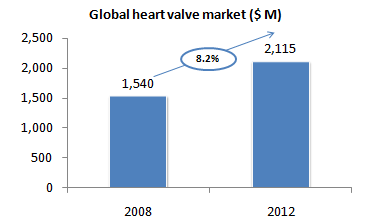

Market size

Trends

- Aortic Valve segment represents 55% of the overall market. However, with 35-50% of patients suffering from severe aortic stenosis considered at high risk for surgery, the current number of patients eligible for TAVI procedures is 200,000 worldwide.

- The TAVI segment thus represents a $2B market opportunity. According to various sources, this market size will be reached in 2014.